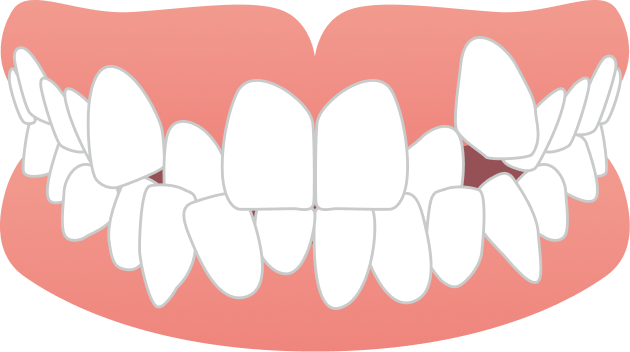

20代女性 ガタガタと噛み合わせが気になる

スタート時19歳の大学生女性の患者さまで、上下の前歯のガタつきに加え、「前歯で噛めない」「噛みにくく食事がしづらい」という機能面のお悩みもあり、ご相談に来院されました。学業や日常生活への影響をできるだけ抑えながら治療を進めたいというご希望を踏まえ、当院で専門的に行っているマウスピース矯正にて治療を開始しました。

BEFORE

| 主訴 | 前歯のガタガタと噛み合わせが気になる |

ガタガタ・八重歯